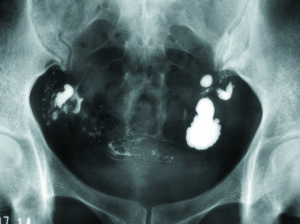

卵管水腫・子宮内膜症:移植の成否を左右する大きな因子です。クラミジアの治療歴がある、帯下(おりもの)が多い(シート常用)、月経痛が強い、嚢腫・筋腫・子宮外妊娠などの手術歴があるなどの場合には、子宮卵管造影やMRIを行い、着床障害・不育症の原因になる卵管水腫・卵管癒着・子宮内膜症などがあれば腹腔鏡検査を行います。

腹腔鏡検査・子宮鏡検査と手術:不妊原因がわからない場合、排卵があってヒューナーテストが正常な場合、何回移植しても妊娠しない場合(反復着床不全)、妊娠しても流産してしまう(反復流産)などの場合には、卵管水腫や卵管周囲癒着などを合併している可能性が高く、腹腔鏡検査や子宮鏡検査が必要となります。

腹腔鏡検査によって異常を認めた場合には、同時に腹腔鏡下手術(卵管開口術、癒着剥離術、子宮内膜症除去術など)を行い、不妊原因をとり除くとともに子宮内の着床環境を正常にとり戻します。

卵管水腫の子宮卵管造影所見